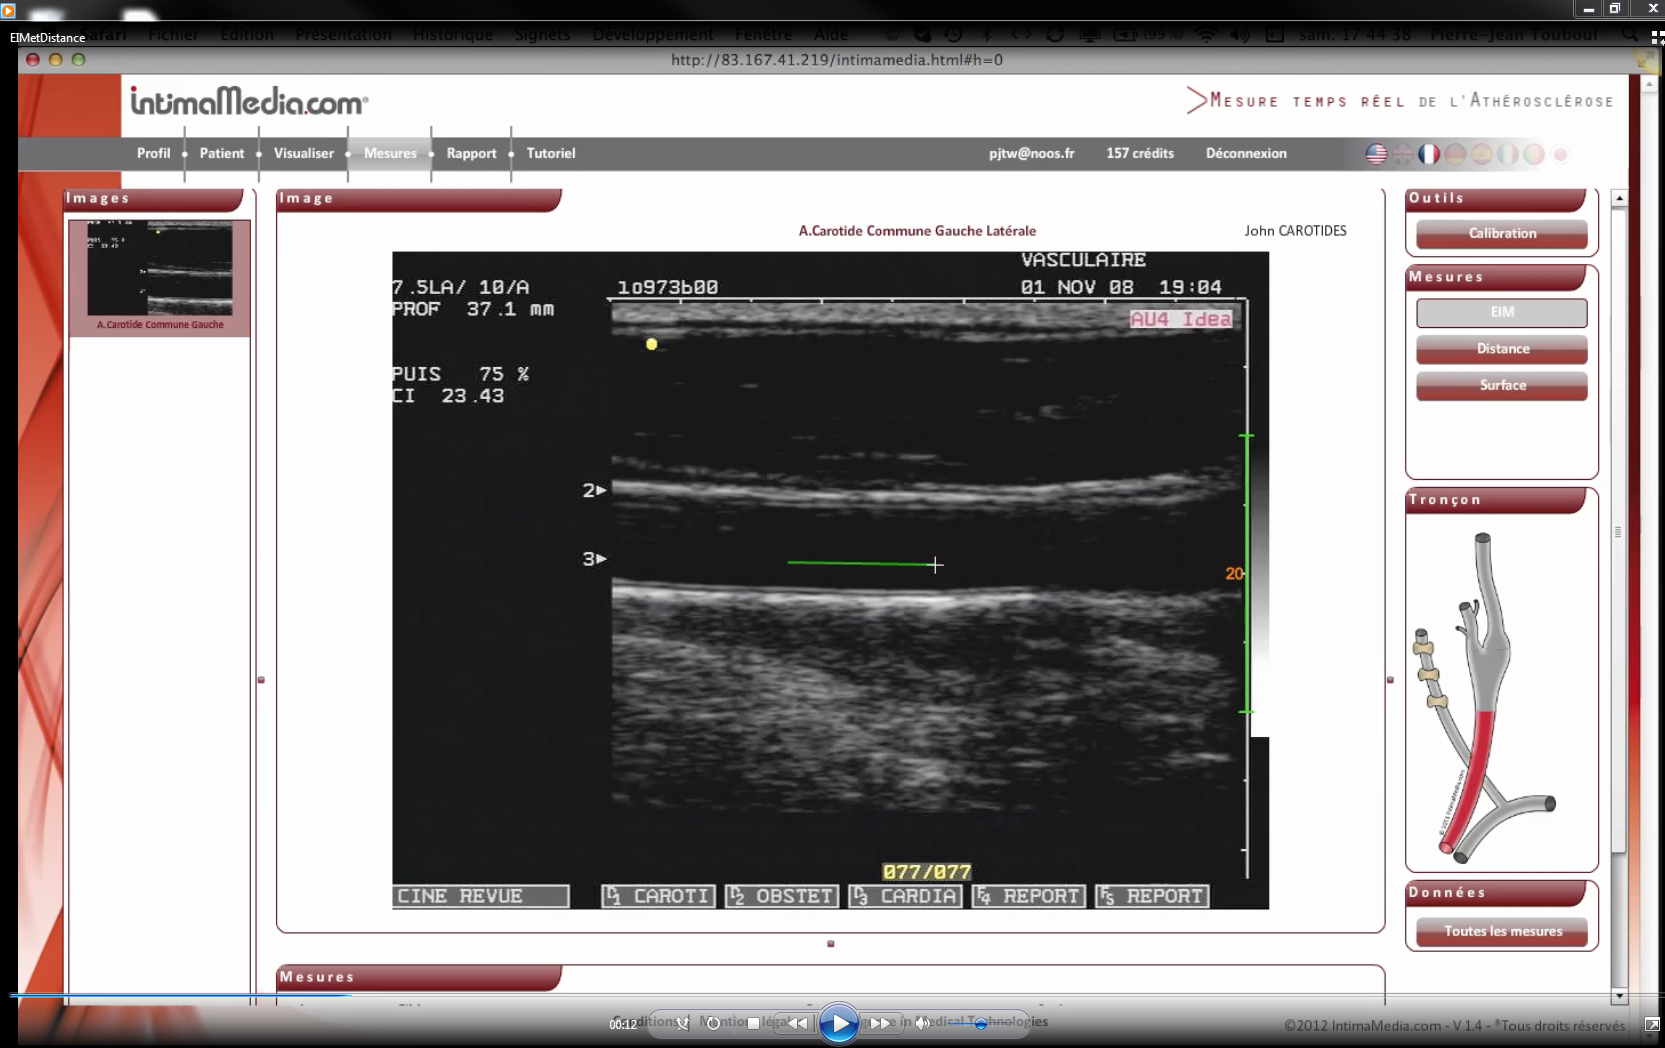

measures.png

589 KB